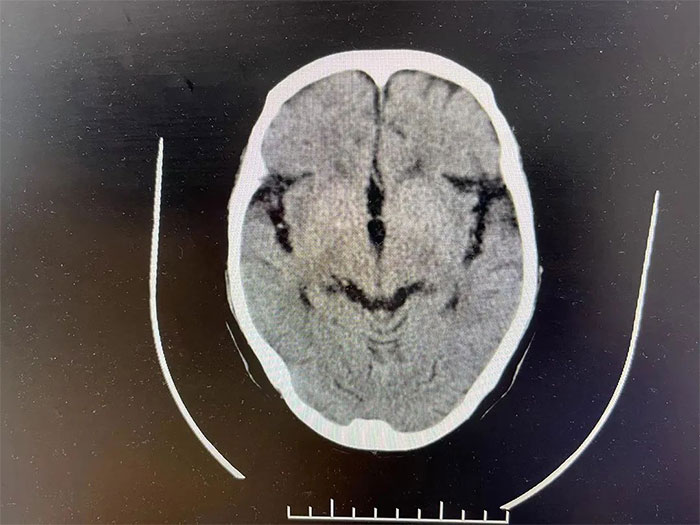

▲ 通过治疗,出血已基本吸收